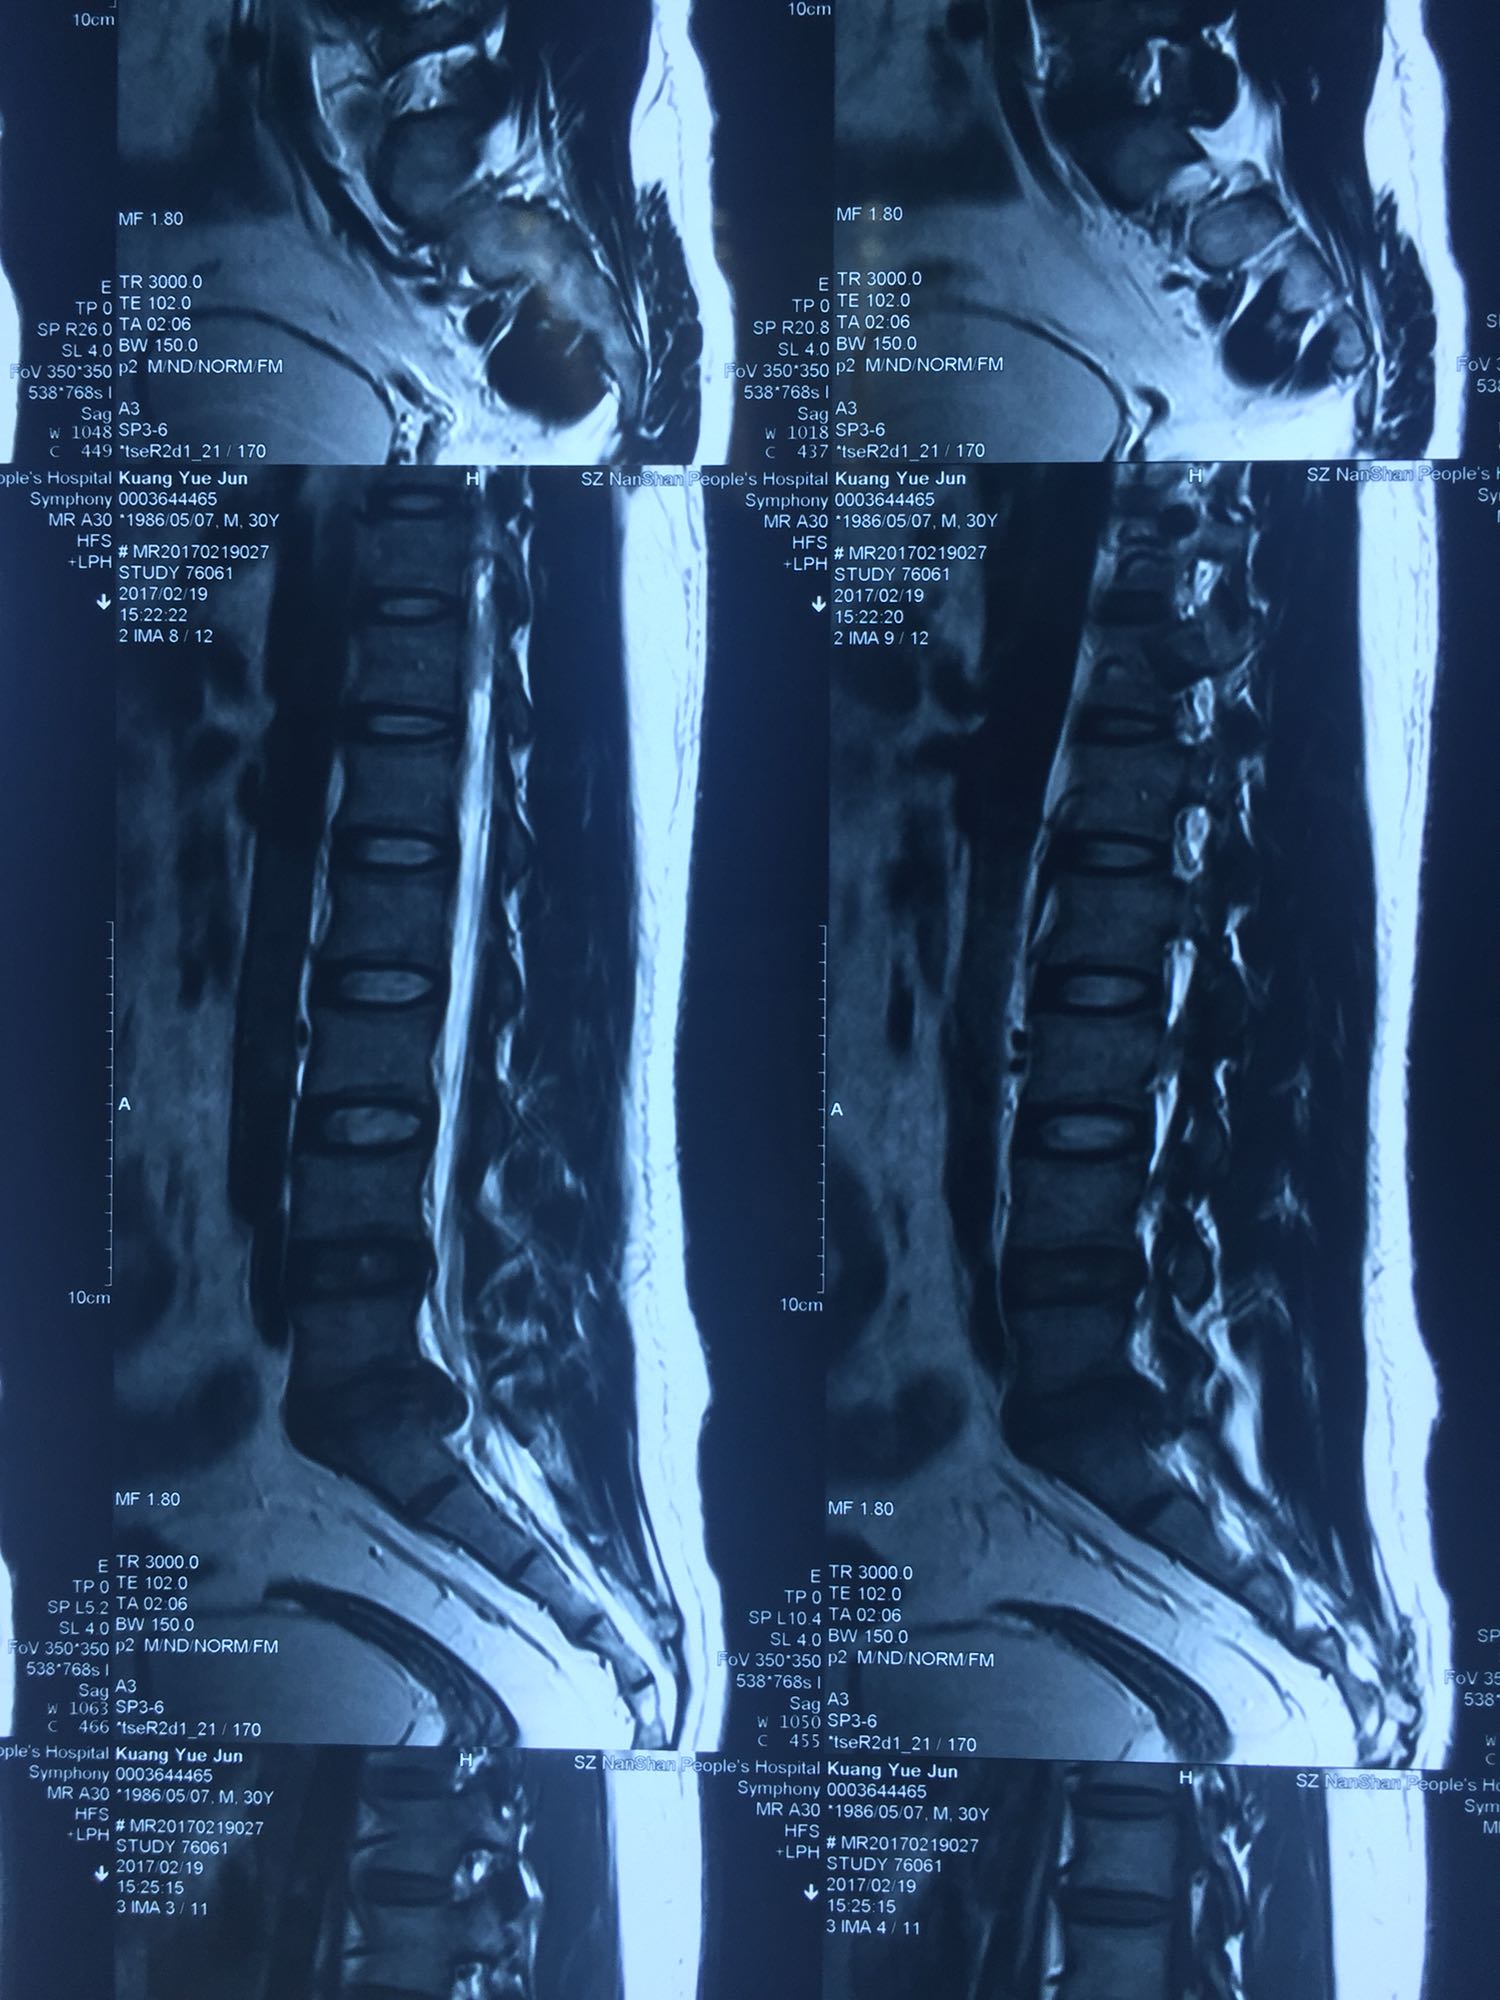

腰骶部肌紧张,腰5骶1棘间及左侧椎旁有压痛及放散痛,左侧坐骨神经出孔处有压痛及放散痛,左侧足背外侧及足底部皮肤感觉麻木,左侧直腿抬高试验阳性(30度)。

诊断:腰5骶1椎间盘突出症 治疗方案:椎间孔镜下经椎板间入路髓核摘除术